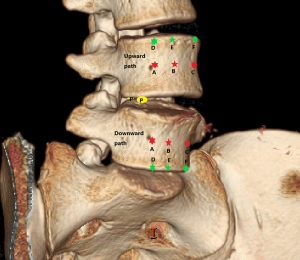

Posterior corner in lumbar spine was selected as the screw entry point (P point) for oblique fixation. The screw entry point (P point) in posterior-inferior corner is the bony area between the upper margin of the pedicle and the upper endplate. The screw entry point (P point) in posterior-superior corner is the bony area between the lower margin of the pedicle and the lower endplate (Figure 2). The corresponding targets are A, B, C, D, E, and F, respectively (A: the middle point of the contralateral anterior-middle 1/3, B: the contralateral anterior-middle point, C: the middle point of the contralateral side, D: the upper point of contralateral anterior-middle 1/3, E: the contralateral anterior-upper point, F: the middle-upper point of the contralateral side) in the contralateral anterior region (Figure 3).

In the process of oblique fixation from posterior corner in lumbar spine, each path could be divided into two groups, medium group and full-length group. The medium group included PA, PB and PC, while the full-length group included PD, PE and PF (Figure 4). The upward paths included PUA, PUB, PUC, PUD, PUE, and PUF. The downward paths included PDA, PDB, PDC, PDD, PDE, and PDF.

In this article, we preset six paths as screw trajectory of oblique fixation from posterior corner in lumbar spine, namely, PA, PB, PC, PD, PE, and PF (Figures 3,4). The design of the pathway is determined by the technical characteristics of spinal endoscopy in clinical practice, considering simultaneously the biomechanical properties of the screw, the longer bone canal and more cortical penetration. The paths should be neither penetrating into the intervertebral space nor making the anterior large vessels injured. Considering the above factors, PE path should be the optimal (longest) path for oblique fixation from posterior corner in lumbar spine.